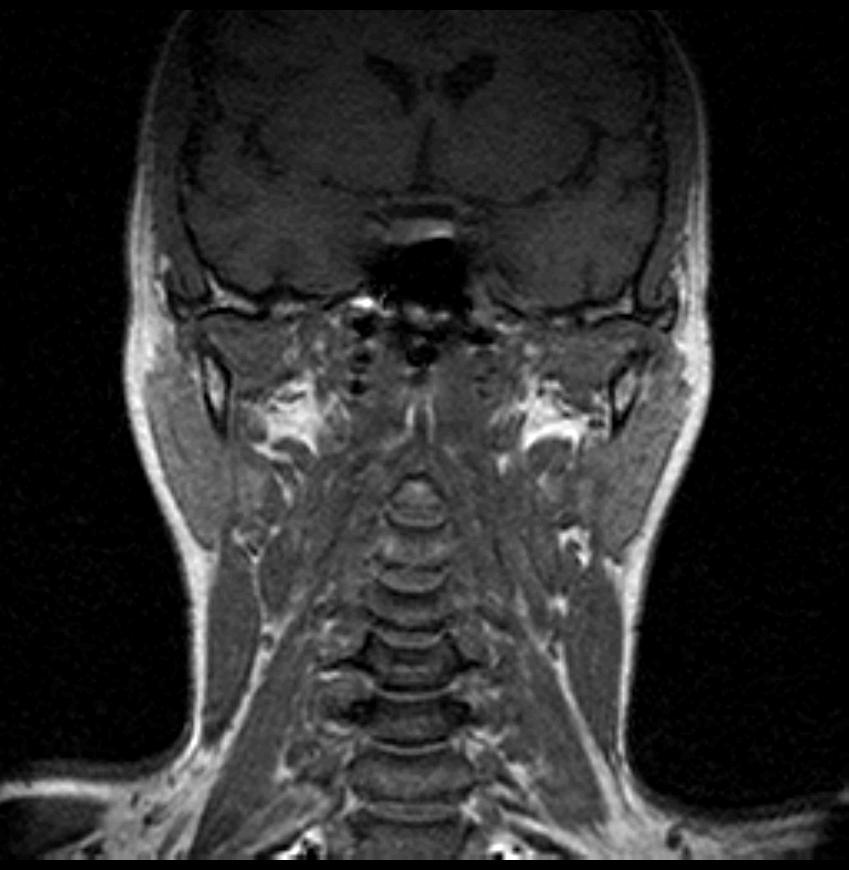

06.06.2011 МРТ - головы и шеи.

Пацентка 36 лет, с жалобами на припухлось в околоушной области справа.

В глубокой доле  правой околоушной железы  на фоне неизмененной паренхимы зона  гетерогенного по Т2, гипоинтенсивного по Т1  с единичными гиперинтенсивными включениями.При контрастировании- накопление контраста диффузное неоднородное и по периферии.Рискну предположить злокачественное образование ( аденокарцинома) с низкой степенью злокачественности( есть капсула, экспансивный рост).Сильно не расстреливайте.

Проблема в том, что перед челюстно-лицевым хирургом стоит распространенность любого объемного процесса, в данном случае все упирается в возмможную травму лицевого нерва и конечно же с дальнейшим его парезом, а ведь женщина  еще молодая. Образование имеет тонкостенную оболочку, по структуре неоднородно, с наличием кальцината, при этом МР-сигнал от окружающих анатомических структур(как костных так и мышечных) не изменен, т.е. об инфильтративном росте речи не идет, в какой то степени доброкачественное. В конкретном случае лицевой нерв с ретромандибулярной веной просто несколько оттеснен.

По гистологии аденома околоушной слюнной железы, но после удаления пока сохраняется парез лицевой мускулатуры, возможно временный.